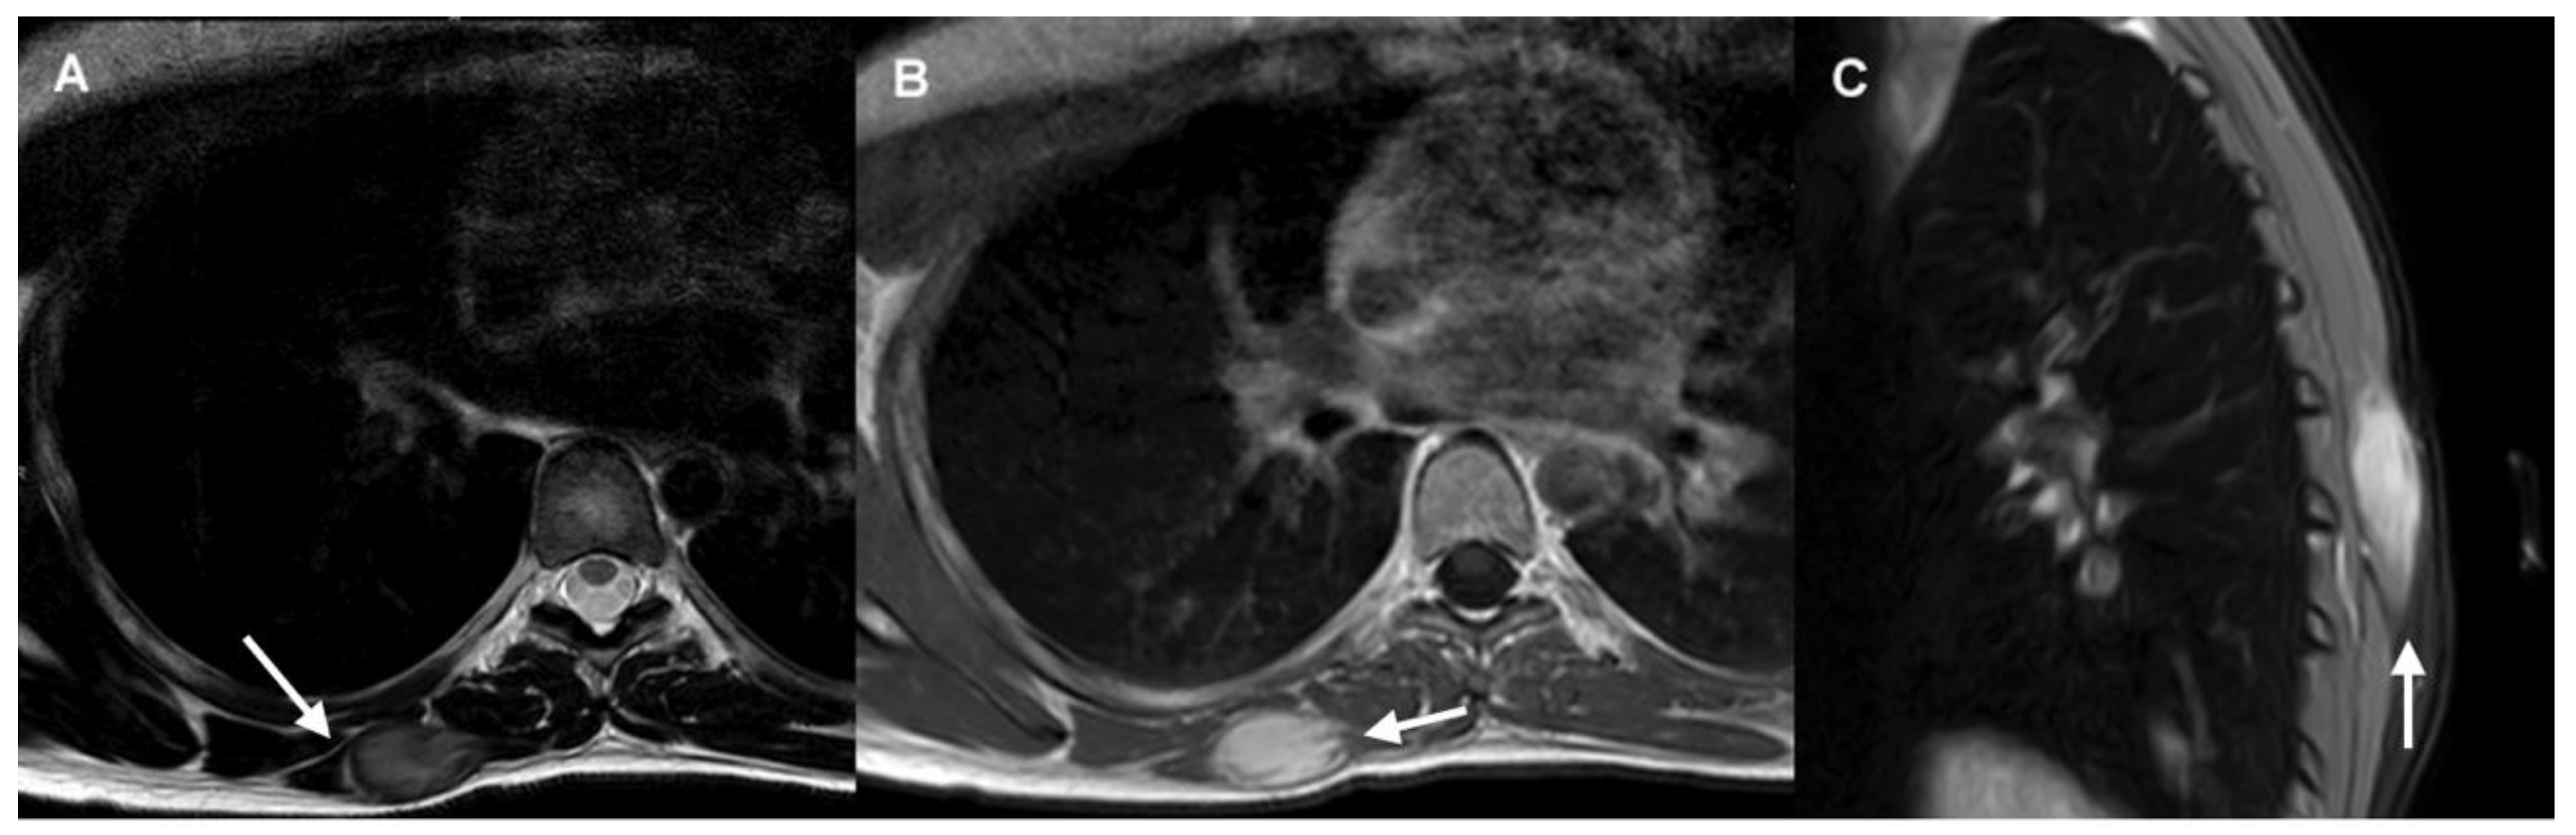

Certain imaging features represent local invasion, such as the “staghorn sign”, which corresponds to intramuscular finger-like extensions, and “fascial tail sign”, an infiltrative border due to linear extension along fascial planes [12]. MRI may also demonstrate the “split fat sign”, which consists of a halo of fat surrounding the tumor (Figure 1).

Figure 1. DT of the right distal trapezius muscle.

• The axial T2-weighted MRI sequence demonstrates a well-defined mass with intermediate signal and hypointense internal collagen bundles. The “split-fat sign” is shown in its lateral margin (arrow).

• Axial post-contrast T1-weighted MRI sequence shows homogeneous mass enhancement and “staghorn sign” (arrow).

• Sagittal fat-suppressed image shows “fascial tail sign” (arrow).